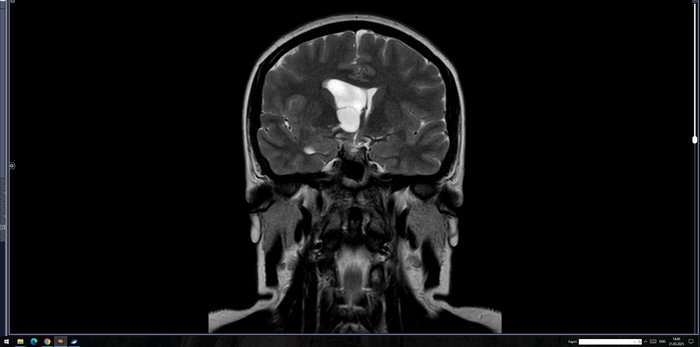

В расширенном турецком седле определяется солидное объемное образование неоднородно повышенного МР-сигнала на Т2 ВИ, размерами до 30 х 25 х 19 мм, неоднородно копит контраст. Образование распространяется в область кавернозных синусов по ходу С5 С6 сегментов внутренних сонных артерий, муфтообразно охватывая их до 70% окружности справа и до 50% окружности слева. Внутренние сонные артерии на уровне образования не сужены. Образование интимно прилежит к задним базальным отделам прямых извилин и зрительному перекресту, больше справа, без его оттеснения. Воронка гипофиза утолщена, отклонена вправо.На этом фоне нормальная структура гипофиза четко не определяется, вероятно, оттеснена вправо и кзади.

Заключение: МР- картина образования гипофиза, соответствует макроаденоме средних размеров с супра- и латероселлярным характером роста. Рек-но: конс. нейрохирурга.